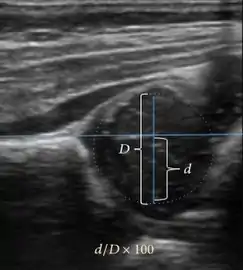

Ultrasound allows categorizing pediatric hips, according to Graf’s criteria, in four main types: normal, immature, and dysplastic (subluxed and dislocated). This classification is based on measurements of the acetabular inclination angle (alpha), cartilage roof angle (beta), and infant age. The femoral head coverage can also be determined by dividing the length of the femoral head covered by the acetabular fossa and the diameter of the femoral head. Its lower normal limits are 47% for boys and 44% for girls (Figure 11).[1]

Figure 11:

Measurement of femoral head coverage.[1]